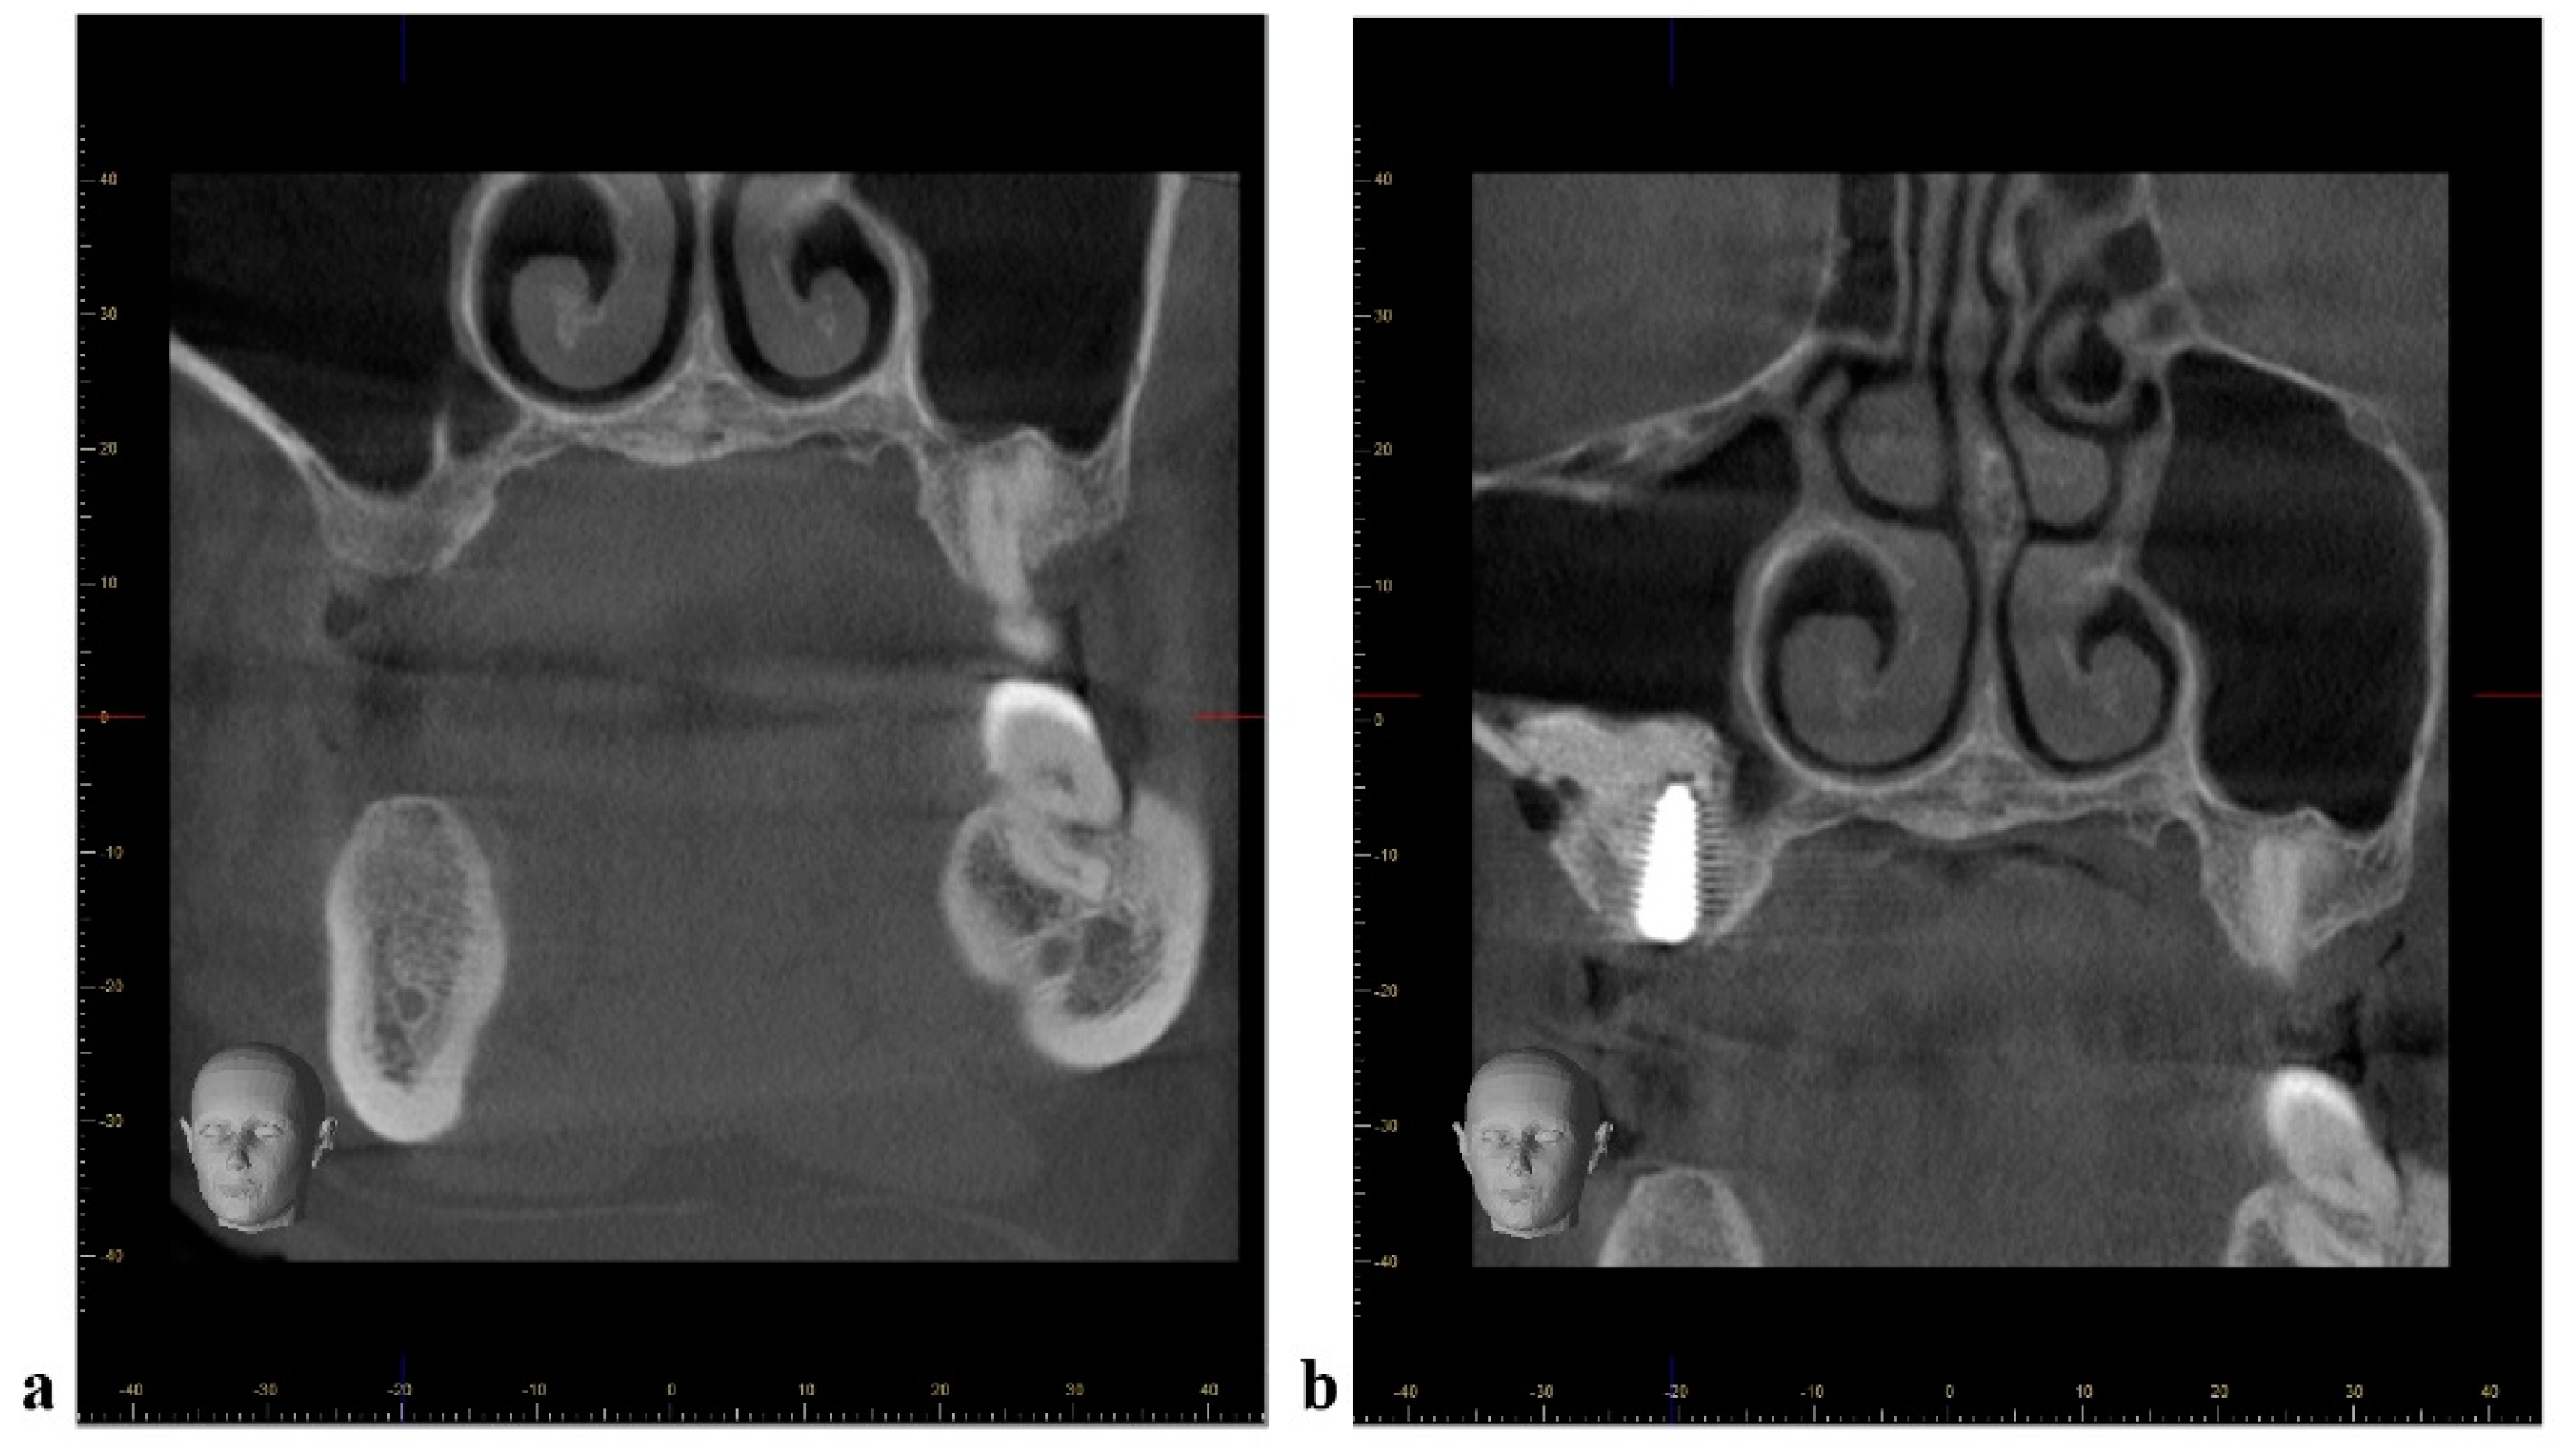

2.3. Radiographic Measurements